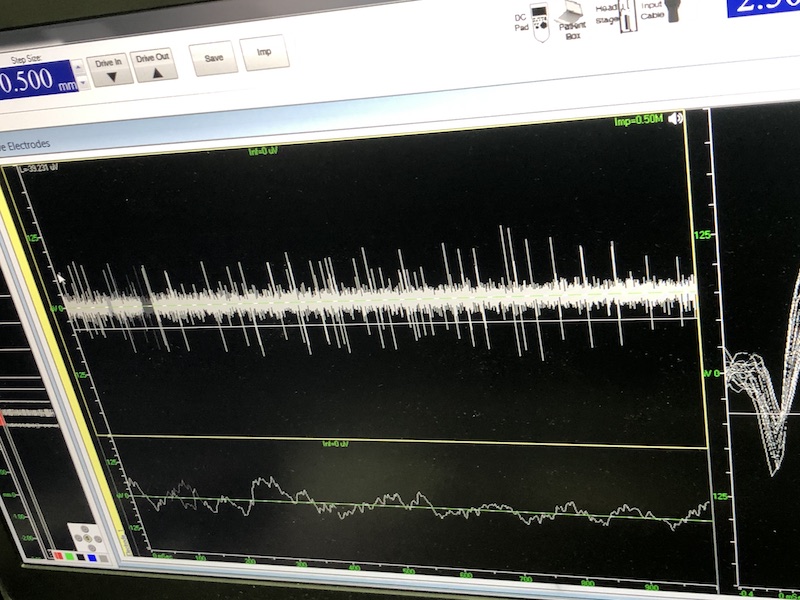

與此同時(shí),檢測電極實(shí)時(shí)記錄電極末端每一點(diǎn)處的電信號(hào),當(dāng)電極逐漸接近手術(shù)規(guī)劃靶點(diǎn)時(shí),借助電信號(hào)的特征,醫(yī)生可以判斷電極是否已經(jīng)沿長軸植入患者顱內(nèi)的目標(biāo)核團(tuán),以及植入的準(zhǔn)確長度。下圖中,檢測信號(hào)屬于典型的核團(tuán)信號(hào),證明電極已經(jīng)抵達(dá)相對(duì)理想的植入位置,記錄下此刻的位置后,即可在相應(yīng)位置植入刺激電極。

alt text

檢測核團(tuán)信號(hào)